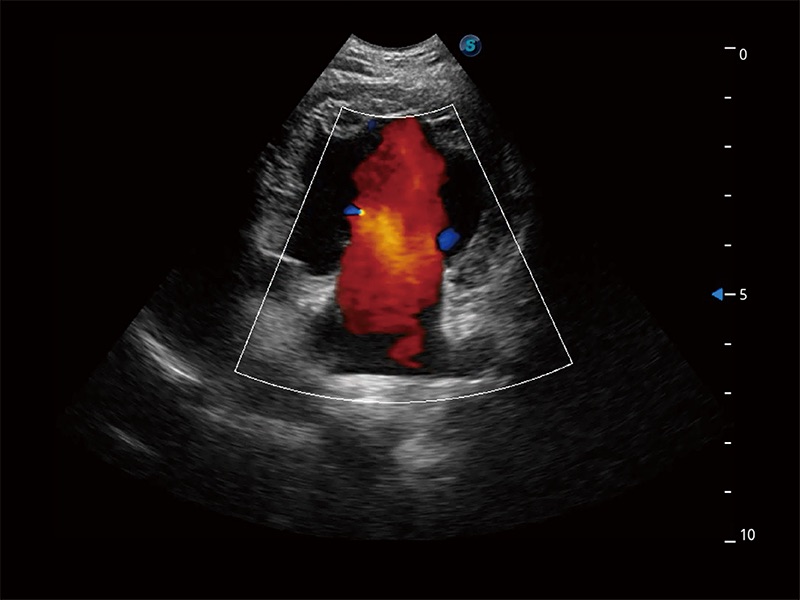

• Bright Flow 立体血流成像

在传统二维血流成像的基础上,呈现血流的立体感,具有动感的生命力之美。即便是微小的血管也能轻松应对,提高了血流的视觉敏感性。

优异的基础图像

ProPet 80 全新的动物超声智能软件和丰富的探头群,为动物医生提供了高清晰度和精细分辨率的图像,无论在宠物、马科、畜牧还是实验室动物等应用中都可以轻松应对,为您的日常工作带来满意的体验。

(犬)二腔心血流